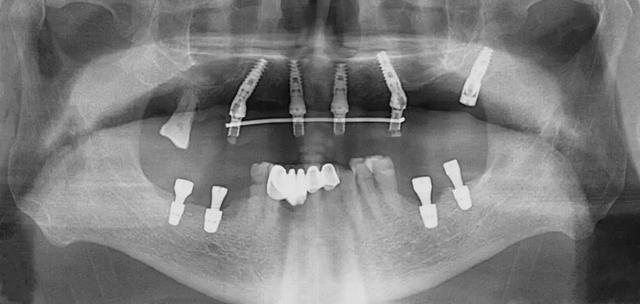

口腔科李德仁主任為老人仔細(xì)檢查了口腔情況,由于缺牙時(shí)間太久,牙床骨量極少,正常的種植修復(fù)需要植骨,手術(shù)創(chuàng)傷大而且半年后才能鑲牙吃飯。建議他進(jìn)行數(shù)字化導(dǎo)板種植,可以不用植骨而且當(dāng)天就能戴牙吃飯,手術(shù)簡(jiǎn)單,創(chuàng)傷小。老人和孩子很信任的接受了李主任的種植方案:上牙床種植5顆,下牙床種植4顆,當(dāng)天戴牙吃飯。

下午2點(diǎn)開始手術(shù),歷經(jīng)90分鐘,一共植入9顆種植體,全程。下午7點(diǎn)用了10多分鐘就完成了假牙安裝,假牙與牙床渾然一體,像是重新長(zhǎng)出的牙齒一般。